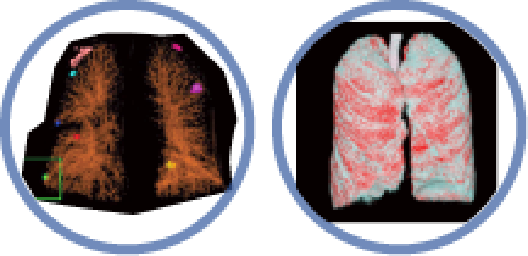

Precision in Pulmonary

▪ Nodule Analysis

▪ Emphysema Analysis

▪ Pneumonia Analysis